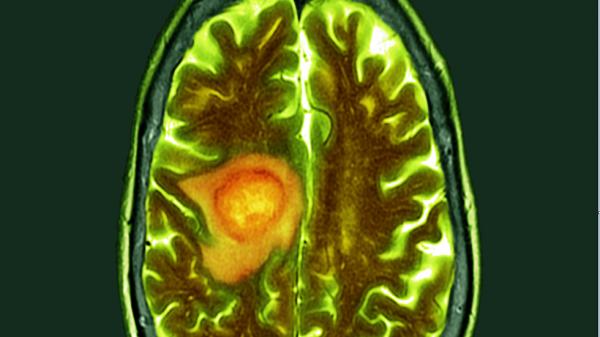

يعتبر الورم الأرومي الدبقي أحد أكثر أشكال سرطان الدماغ شيوعا وخطورة، وهو أحد أصعب أنواع سرطان الدماغ. ومع ذلك، قد تكون هناك أخبار سارة في الأفق.